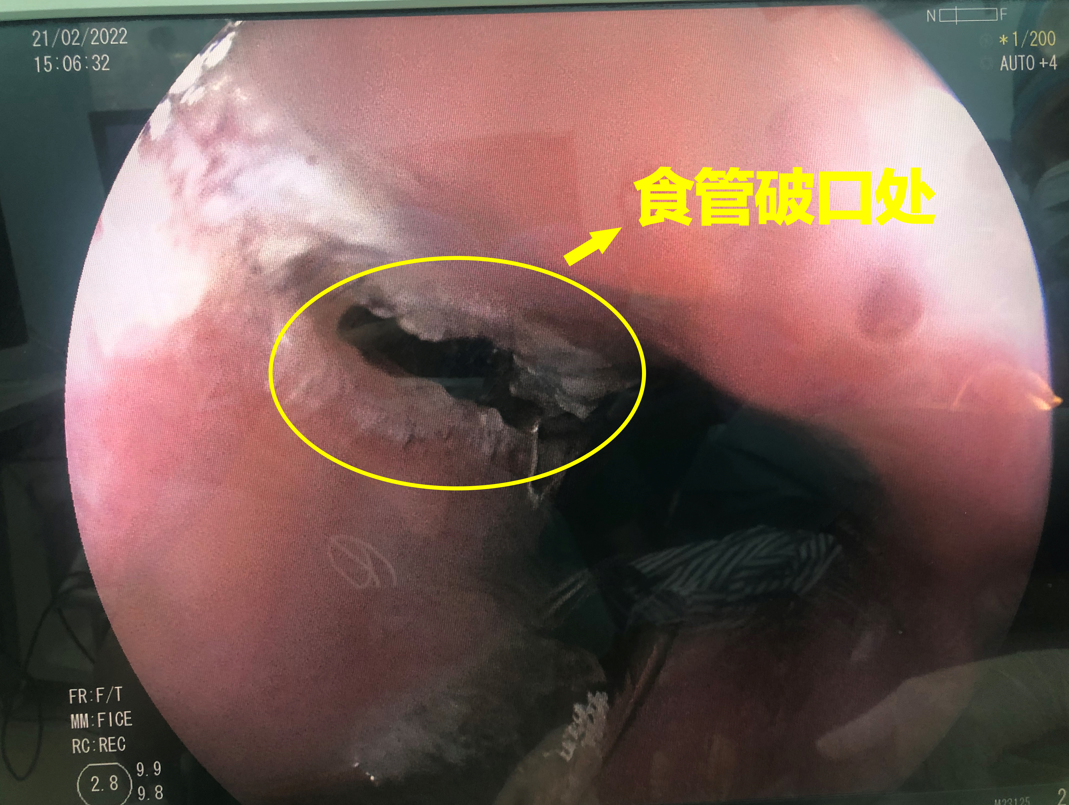

"综合考虑,我们觉得很有可能是食管破裂.